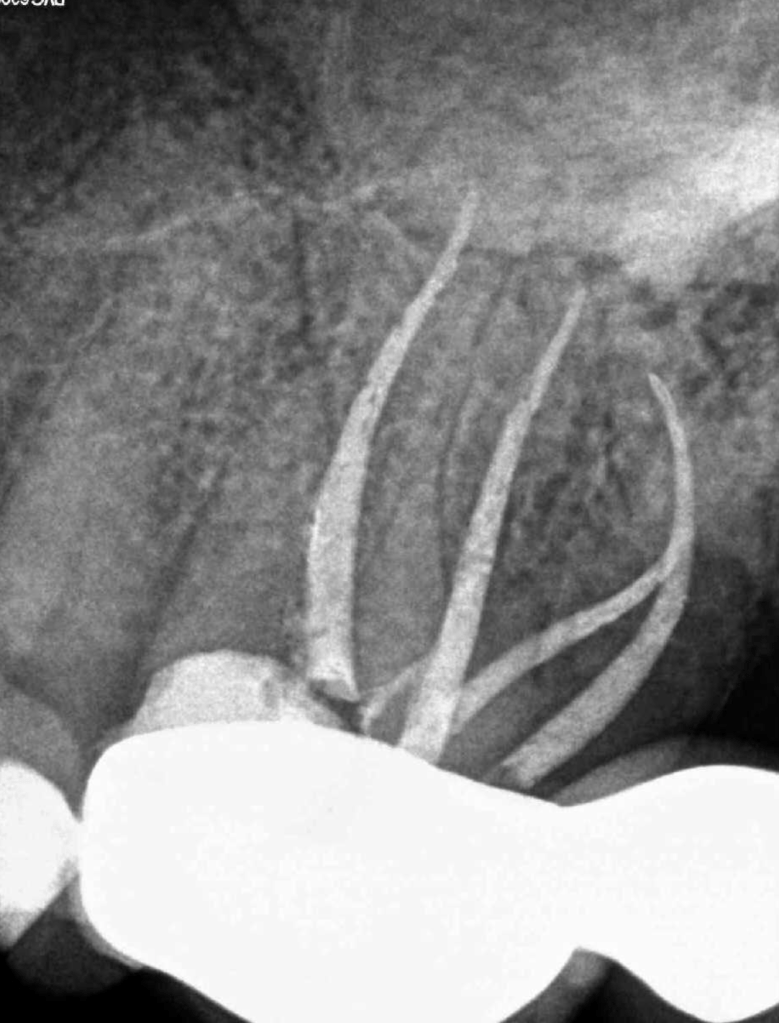

Vertical root fracture